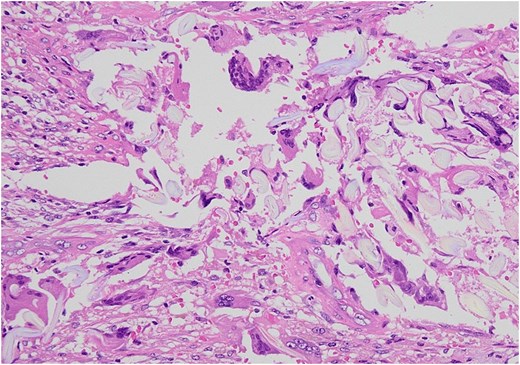

Surgical specimen. The presence of gauze-like fibrous tissue is noted accompanying the granuloma (arrow).

Microscopic examination showed by H&E × 200 staining. Foreign body granuloma containing a piece of gauze and giant cells.